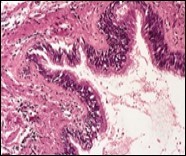

Figure 2.Ciliated cutaneous cyst with an undulating layer of ciliated cuboidal epithelium and supporting fibrous tissue framework (12).

Figure 3.Ciliated cutaneous cyst with a coating of plump, ciliated columnar epithelium and a circumscribing fibro - connective tissue (12).

Cystic structures cogitated within deep dermal or subcutaneous tissue can be impacted with haemorrhagic fluid. Cyst lining is smooth, regular and is essentially composed of a singular layer of columnar epithelium with focally pseudostratified columnar epithelium, a circumscription of loosely configured, well vascularized, fibroconnective or fibrocollagenous tissue and an absence of inflammatory infiltrate.

Alternatively, cutaneous ciliated cyst can be lined by non ciliated cuboidal or columnar epithelium with intermingled intercalated, dark or round peg cells. Foci of squamous metaplasia can be occasionally exemplified in the adherent epithelium whereas mucinous cells or apocrine-like features are exceptional 6, 8. Figure 1, Figure 2, Figure 3, Figure 4, Figure 5, Figure 6, Figure 7, Figure 8, Figure 9, Figure 10, Figure 11, Figure 12. 11, 12, 13, 14, 15, 16, 17, 18, 19.